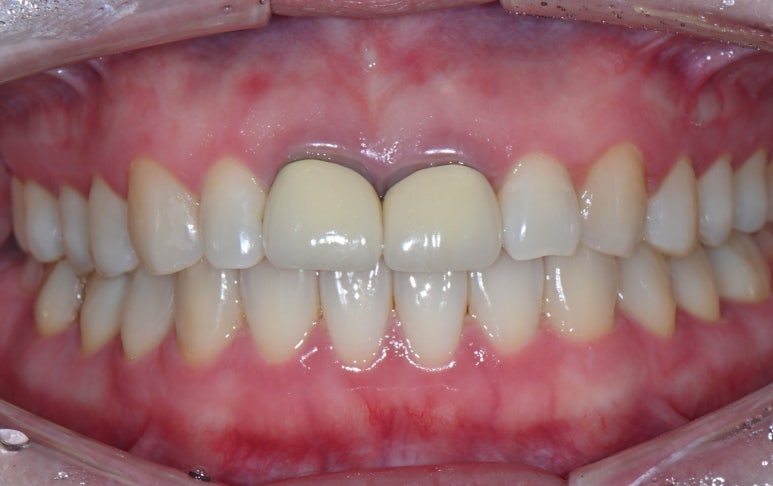

5. 최종 크라운 장착

새로 제작된 크라운을 장착합니다.

환자분께서 색상과 모양에 만족해하셔서 특별한 수정없이

치료를 마무리할 수 있었습니다.

25.09.11 치료 후